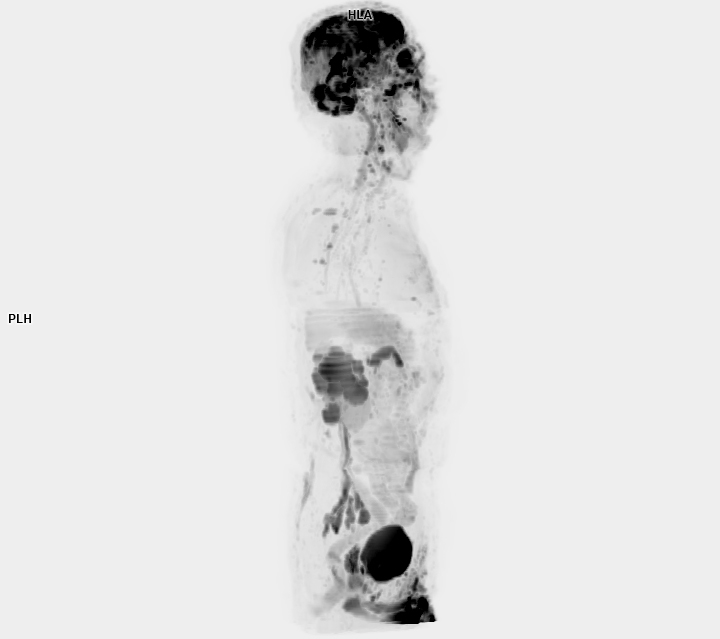

3 Tesla MR Çekim Görüntüleri

• 3 Tesla MR Çekim Görüntüleri